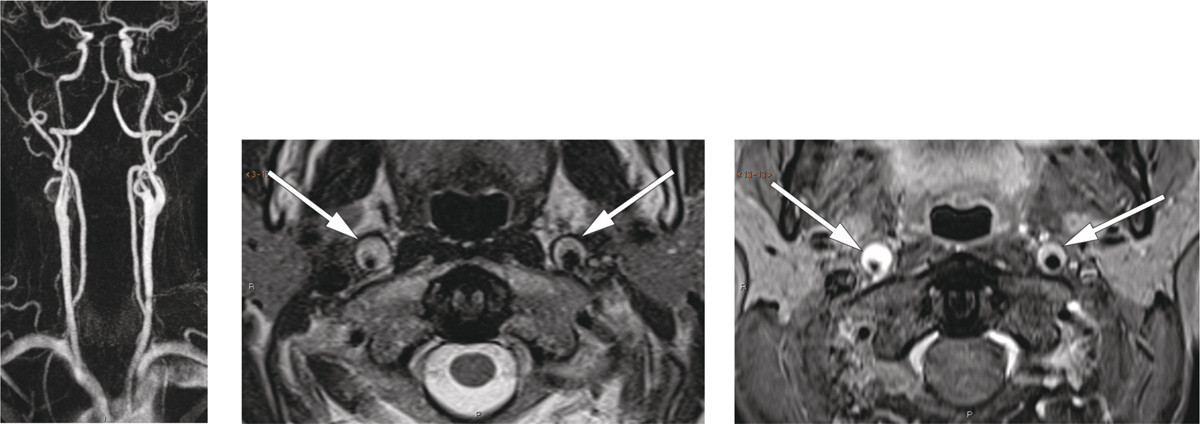

Nevrologisk undersøkelse avdekket Horners syndrom. CT-angiografi viste fortykket karvegg i begge a. carotis interna, mest uttalt på høyre side, fra like over bifurkaturen til skallebasis. MR-angiografi og T2-vektede bilder bekreftet bilateral carotisdisseksjon, med minste lumendiameter 2 mm på høyre side (bildet til venstre og bildet i midten). Fettsupprimerte T1-vektede bilder (bildet til høyre) viste høyt signal i arterieveggene, forenlig med intramurale hematomer.